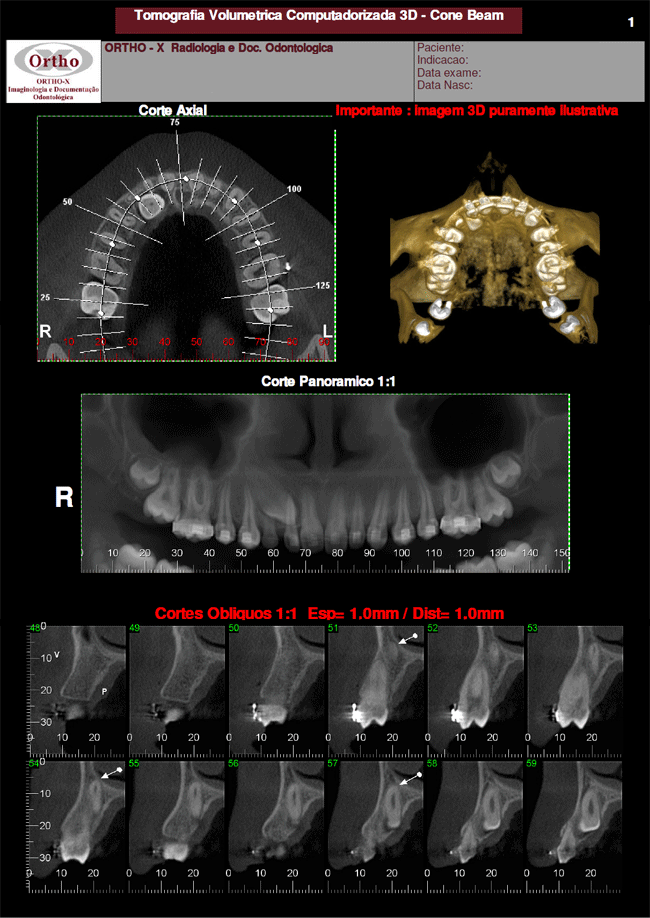

Exemplo de Exames: Dente Incluso